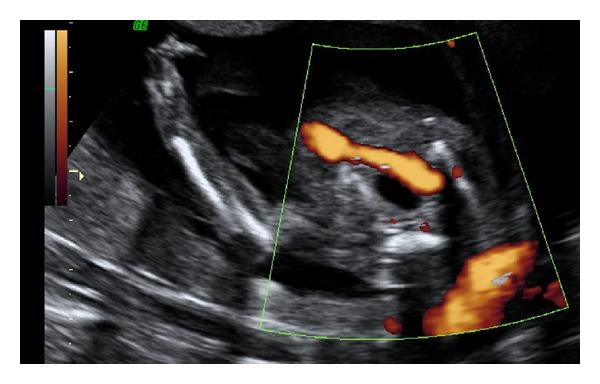

The value of a single umbilical artery (SUA) in first trimester ultrasound is not well established. The aim of our study was to determinate the relevance of diagnosis of single umbilical artery in first trimester ultrasound as an early marker suggesting the presence of malformations or associated chromosomopathies.

Prevalence of SUA was 1.1% in single pregnancies and 3.3% in twin pregnancies. Sensitivity, specificity, false positive rate, and false negative rate for the finding in the first trimester were 84.2, 99.8, 0.2, and 15.7%, respectively. 17.6% of cases had associated malformations. With an ultrasound in the 16th week most of the cases with significant fetal malformation were diagnosed.

SUA is a useful marker in the first trimester for fetal malformation pathology, as it will allow detecting a large number of cases with malformations before 20 weeks of gestation.

早孕期超声检查中单一脐动脉(SUA)的价值尚未明确确立。我们研究的目的是确定早孕期超声诊断单一脐动脉作为提示存在畸形或相关染色体病的早期标志物的相关性。

单胎妊娠中SUA的患病率为1.1%,双胎妊娠中为3.3%。早孕期该发现的敏感性、特异性、假阳性率和假阴性率分别为84.2%、99.8%、0.2%和15.7%。17.6%的病例伴有相关畸形。在孕16周进行超声检查时,大多数有严重胎儿畸形的病例得以诊断。

SUA是早孕期胎儿畸形病理学的一个有用标志物,因为它能在妊娠20周前检测出大量有畸形的病例。